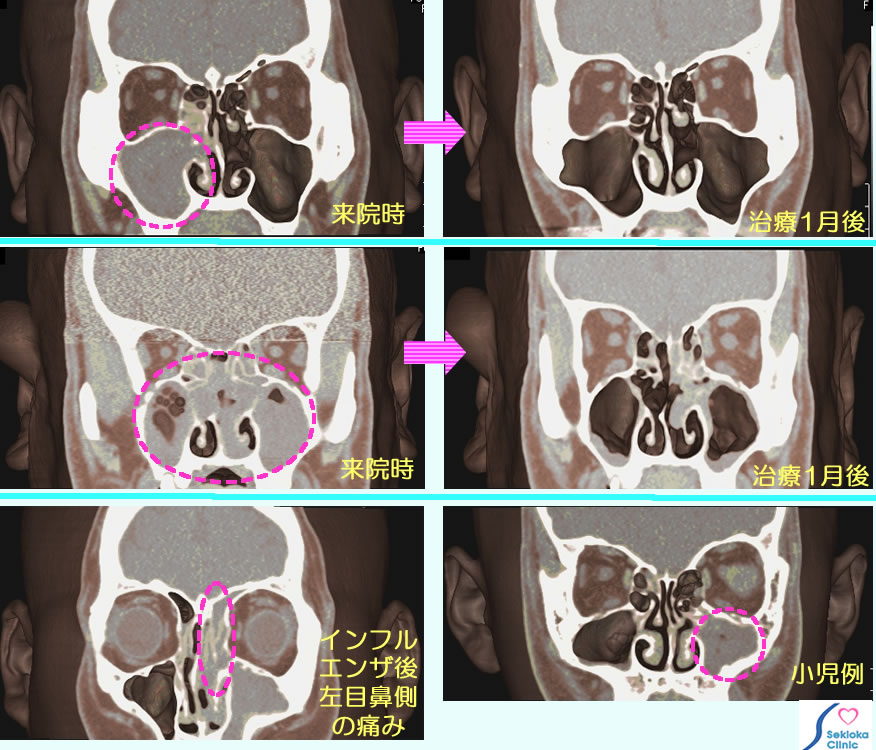

| 自覚症状 | 繰り返す咳、喉の不快感で受診される方が多い。”風邪が長い”、”風邪の市販薬を服用していたが改善しないので受診した”と言われる方も度々ある。これらは鼻汁が喉に降りる(後鼻漏)症状で、前方に鼻が出るとは限らないので風邪と誤解されるようである。中には夜間、鼻がつまって寝苦しい(挿入画像の中段例)や鼻のにおいが臭い(上段の画像)や鼻声などで受診される例もある。 |

| 診断 | CTが治療方針を決めるには信頼度が最も高いと米国の教科書では書かれている。病巣の部位、広がり、時には腫瘍含めて、正確に評価するにはCTである。以前はX線撮影も使われたが正確とは言えない。最下段左側に インフルエンザ後、左目の鼻側に痛みが出現して受診され、MDCTで検査したことろ、師骨蜂巣に広がる副鼻腔炎であることが判明した例を示します。MDCTは3次元の画像なので 診断に都合よい任意方向から観察できます。 |